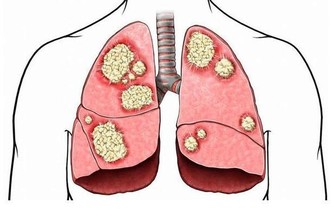

如果你天天熬夜到 1 點多,肝回不了血,有毒的血排不掉,新鮮的血生不成,膽又無法換膽汁,

所以這些人容易得膽結石、囊腫、大三陽、小三陽各種病癥。

在歐洲地區,平均四個人就有一個肝炎攜帶者,這就叫不懂規則。